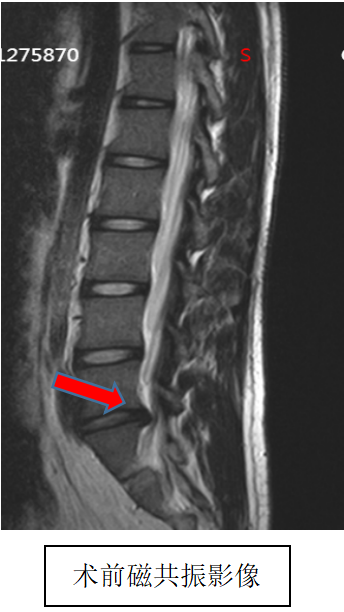

吴静晔主任是成人ai 派驻郑州医院的脊柱外科专家,也是成人ai 脊柱外科的执行主任,在为小明做了全面检查后,结合术前 MRI 精准定位病变部位,在充分沟通诊疗方案与风险后,为小明实施了微创手术,精准解除神经压迫。

术后即刻复查磁共振显示,手术达到预期效果,小明的疼痛快速缓解,麻木感逐渐消退,终于能正常坐立、平稳走路。